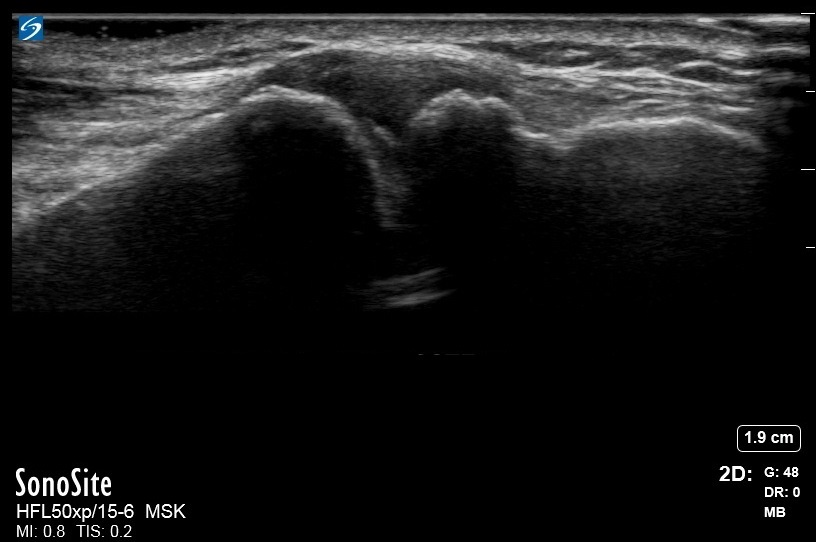

肩変形性関節症肩鎖関節 (AC) 共同イメージ